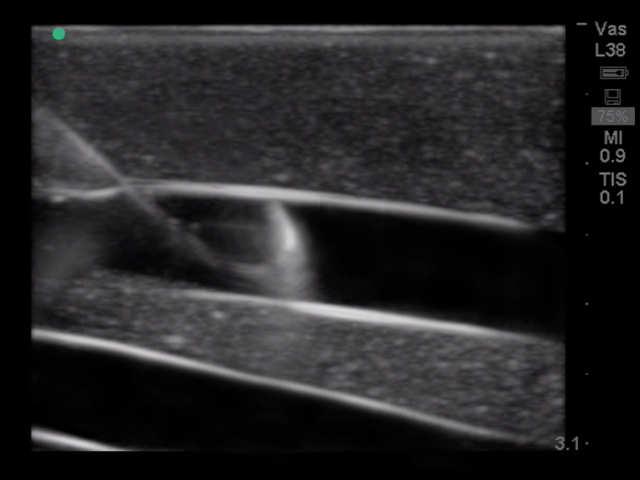

超声引导下颈内中心静脉穿刺术超声训练模块

型号:PC-BP009/PC-BP009.01

模型提供了极佳的真实感,给练习中心静脉置管术提供了最为经济实惠的操作模型